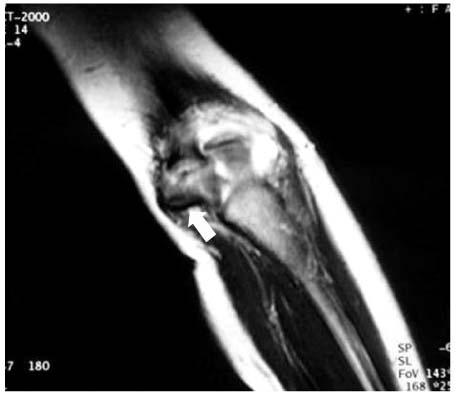

Fx: Fracture, Dx: Diagnosis, MCF: Medial condyle fracture, MRI: Magnetic resonance imaging, Intraop.: Intraoperative, OR/IF: Open reduction and internal fixation, LOM: Limitation of motion, ROM: Range of motion.